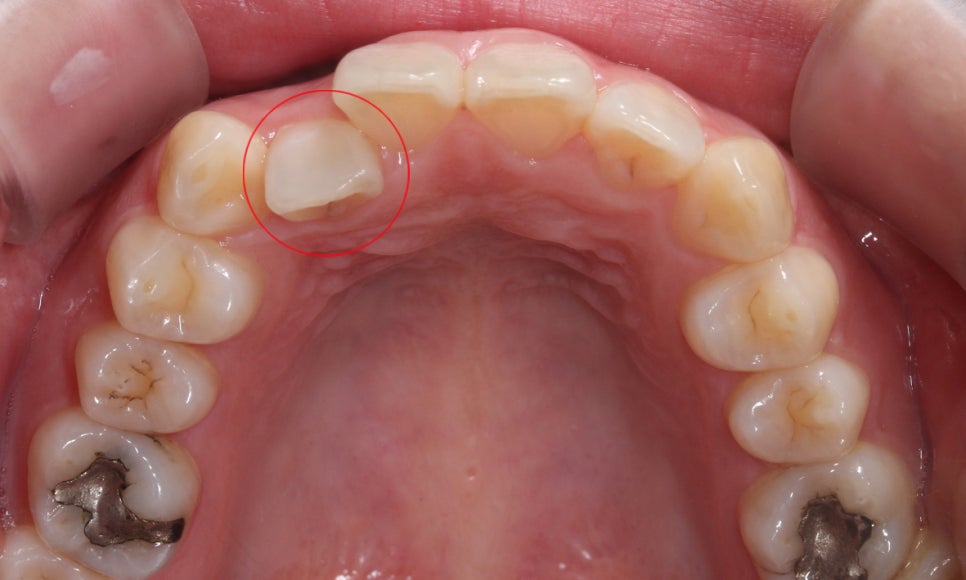

상악의 치아 배열을 보시면 우측 측절치가

설측으로 틀어져 있는 모습인데요,

안쪽으로 뻐드러진 측절치를 정상각도로

교정하고 튀어나온 송곳니를 덧니교정하여

상악의 치열을 바로잡기로 하였습니다.

하악의 경우 전치부에서 약간의

Crowding이 발견되는 모습입니다.